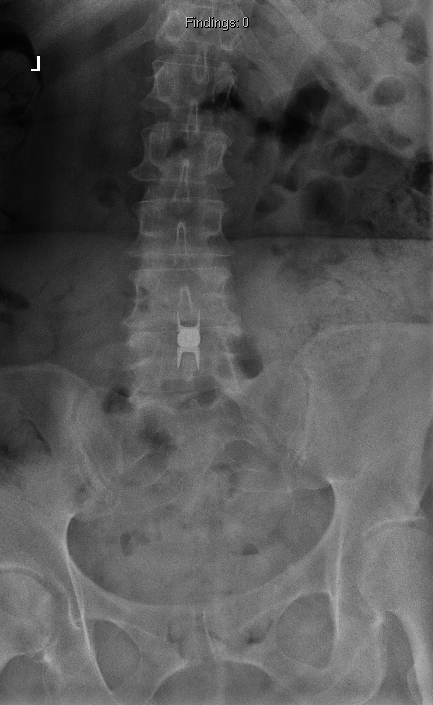

Case 1, Part 2: The patient had a #Vertiflex procedure done elsewhere; symptoms worsened, now can't stand upright, uses walker. Thoughts on her treatment so far? Next steps? #MedTwitter #Orthopedics #orthopedicsurgery #neurosurgery #spine #spinehealth #spinesurgery #scoliosis

Case 1, Part 3: For our patient with worsening #spondylolisthesis, We chose L3-S1/ilium reconstruction with TLIF L4-S1. Great news! She can now stand upright without needing a walker. 🌟🩺 #SpineSurgery #BackPainRecovery #MedicalCommunity